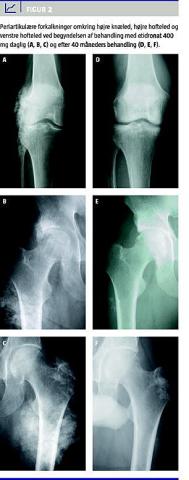

En dansk mand, der var født i 1965, med kronisk nyresvigt (CKD) på grund af ekstrakapillær glomerulonefritis blev hæmodialyseret i perioderne 1984-1987 og 1989-2001. I mellemtiden havde patienten et fungerende nyregraft. I 1993 blev der registreret ekstraskeletale forkalkninger omkring ankler, knæ, hofter, skuldre og albuer, og de var ledsaget af svære smerter og nedsat bevægelighed af leddene. Knoglebiopsi fra 1994 viste renal osteodystrofi med hyperparatyroide læsioner uden tegn på defekt mineralisering eller aluminiumosteomalaci. I 1995 blev der foretaget total paratyroidektomi. Præoperativt var plasma-parathyroideahormon (p-PTH) 14-23 pmol/l, plasmafosfat (p-P) 2,10-2,90 mmol/l og ioniseret kalcium (p-Ca++) 1,25-1,30 mmol/l under behandling med fosfatfattig diæt, alfacalcidol, fosfatbinder og lav-kalciumkoncentration i dialysevæsken (1,25 mmol/l). PTH faldt efter paratyroidektomien, men steg efterfølgende til det præoperative niveau (Figur 1 ). Fra 1995 til 1998 gennemgik patienten 15 operationer med ekstirpation af forkalkningerne omkring knæ, hofter, skuldre og albuer. Pga. gentagne recidiver og postoperative komplikationer forsøgte man behandling med etidronat 400 mg daglig fra maj 1998. Behandlingen fortsatte uafbrudt i 42 måneder. Figur 1 viser, at p-P faldt gradvist under behandlingen. P-Ca++ steg forbigående, og i samme periode faldt p-PTH svarende til en forbigående øgning i dosis af alfacalcidol. Leddene blev røntgenundersøgt før start og derefter jævnligt under behandlingen (Figur 2 ). Efter tre måneder var forkalkningerne aftagende, og efter 36 måneder resterede kun mindre forkalkninger omkring hofterne. Symptomerne var på det tidspunkt helt forsvundet. Der blev ikke registreret bivirkninger af behandlingen. I december 2001 blev patienten nyretransplanteret, og behandlingen med etidronat ophørte. Graftens funktion har efterfølgende været stabil, og kalcifikationerne er ikke recidiveret.